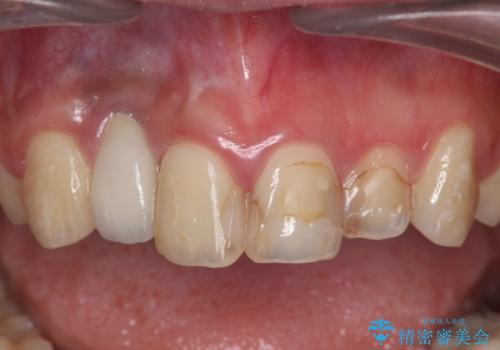

- 虫歯の治療を繰り返した前歯の見た目の改善を求めて来院されました。

大きく詰められたコンポジットレジンと虫歯の再発が見られ、経年劣化により審美性も損なわれていました。

充填されたコンポジットレジン・再発した虫歯を神経に影響が出ないよう丁寧に除去し再充填をしたのちオールセラミッククラウンで前歯の審美性を回復します。